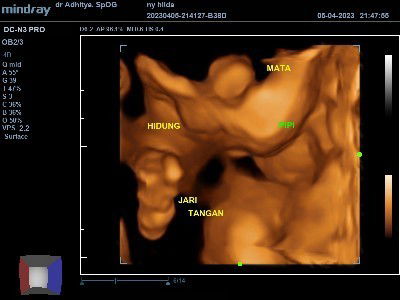

Hpl juni usg nya gimananih? Wajah adek terlihat jelas/gak? 🥰

Udah berkali2 usg 4D gak ada yg beruntung,pasti wajah adek kalau nampak depan ketutupan sama tangan/kakinya hehe, ini pas usg 31 w.